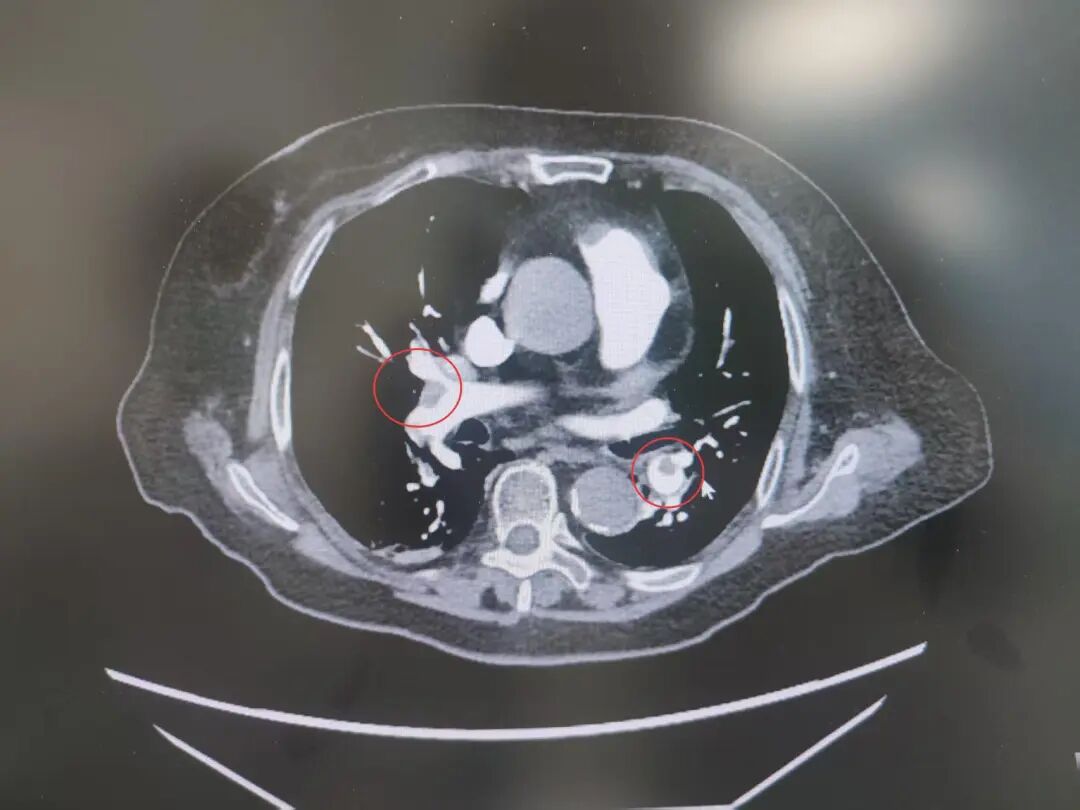

患者高血压病史7年,最高血压达190/100mmHg,2型糖尿病7年,控制不佳。发病前3天,意外摔伤致股骨颈骨折,后出现咳嗽、呼吸困难、胸痛等症状,被紧急送到我院急诊。完善相关检查后,明确诊断为中高危肺栓塞——这是一种足以危及生命的急症,病情进展迅速。

肺占位

为进一步精准救治,呼吸与危重症医学科宋刚主任带领团队对患者进行全面评估,结果令人揪心:肺血栓栓塞(中高危)、I型呼吸衰竭、肺占位性病变、急性冠脉综合征、急性肾功能不全、肝功能不全、脓毒症等多种疾病,且随机血糖高达31.68mmol/L,远超正常范围,生命体征岌岌可危。